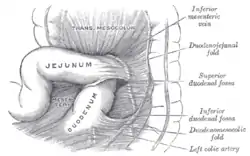

Superior and inferior duodenal fossæ.

Superior and inferior duodenal fossæ. Duodenojejunal fossa.

Duodenojejunal fossa.